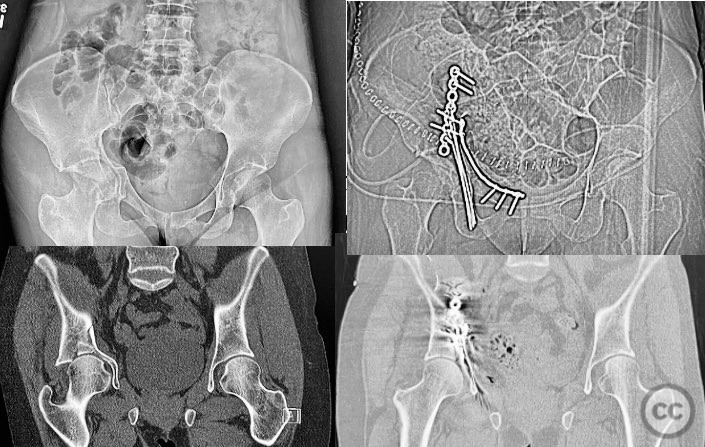

Clinical and radiological findings:  An active senior patient sustained an intruded acetabular fracture, best classified as an anterior column/posterior hemi-transverse (AC/PHTr) pattern with associated medial dome impaction. Initial evaluation included clinical and radiological assessment, with CT imaging confirming the fracture configuration and impaction zone. Neurovascular examination was not specified. Skeletal traction of 10-15 pounds was applied during initial resuscitation and evaluation.

Planning remarks:  The preoperative plan involved open reduction and internal fixation (ORIF) via an ilioinguinal approach. The surgical objective was anatomical reduction of the anterior column and posterior column, buttressing the quadrilateral surface, and addressing the medial dome impaction with allograft bone support. Preoperative imaging was used to plan fragment-specific reduction and fixation.